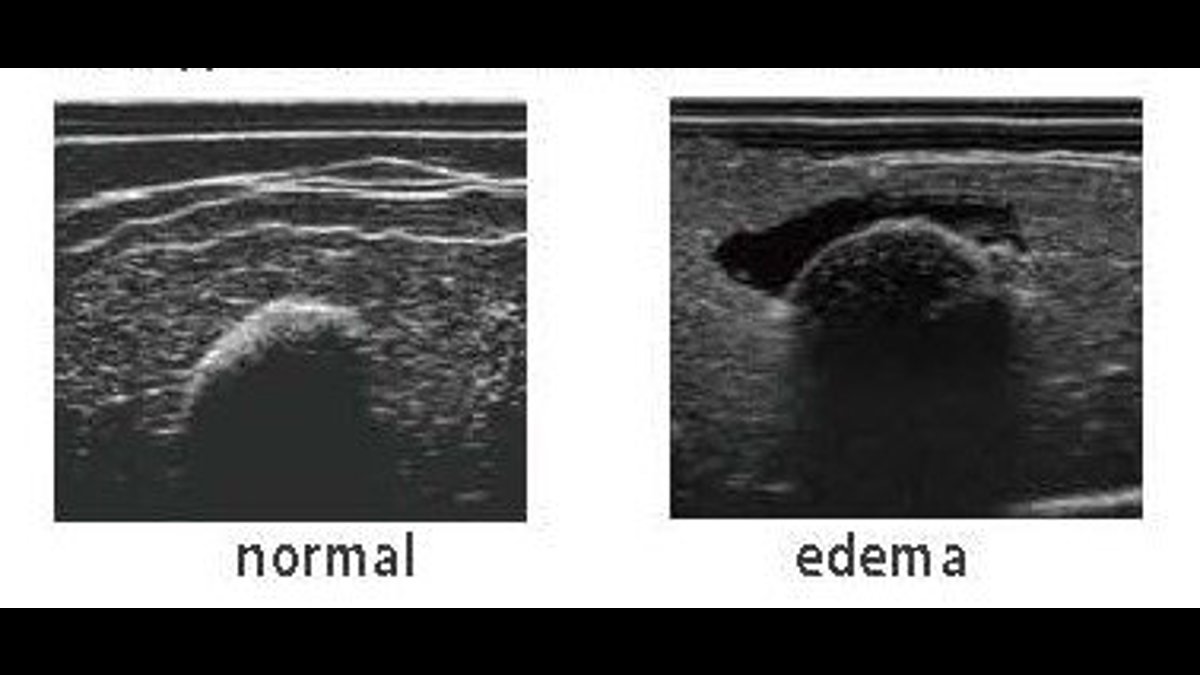

- Assessment of deep tissue by ultrasound (edema in the sciatic area)

- also includes two echo pads, one with edema, and one normal

- Ultrasound compatible sciatic inserts

- Sciatic pressure sores can be viewed under ultrasound